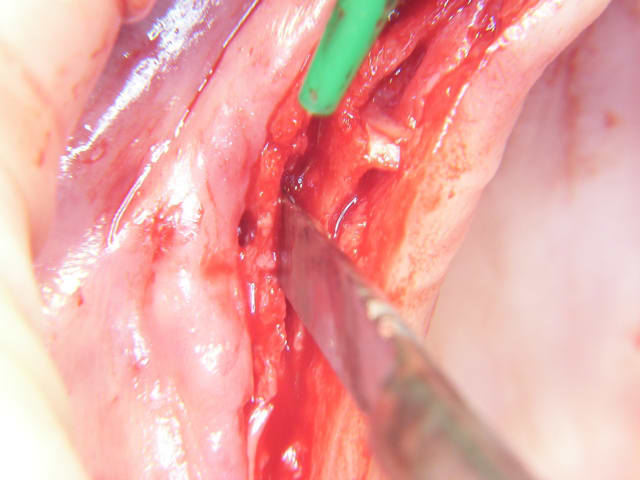

le résultat:

le D1 c'est pas top pour l'expansion, mais:

ouverture crête au disque diam

piezzo jusqu'à 10 mm

fraise tungstène 10/12 mm

tentative avec expanseur meissinger : crête trop raide

deux décharges de part et d'autre de 46

expansion et facture non déplacée le morceau étant avec le périoste

une fois la crête expansée, foret 3.4 sur 13mm

et en mettant l'implant: crac la partie "fêlée" décide de se faire la malle.

vis d'ostéo (galère car je n'avais pas "pré-foré" le greffon :petite écaille partie sup)

vis en place

sculpture des bords du greffon pour supprimer les angles saillant.

vitalos

sutures

pour la douleur, en général aucune suite particulières avec l'expansion, quelques fois douleurs qui je crois sont dues au mat de comblements (j'avais déjà le problème avec le tcp si en contact avec le périoste